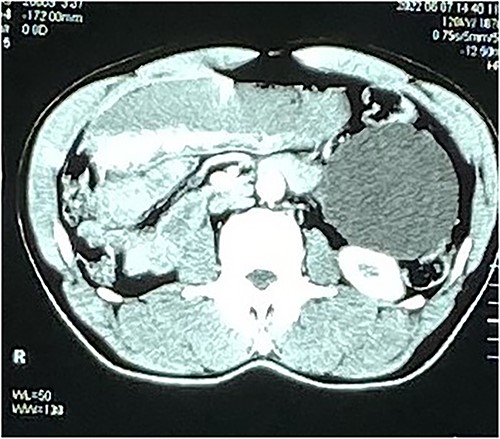

Routine laboratory investigations were done with the following values: HB 14 g/dl, WBC 3.4 × 103 u/l, neutrophils 30.8%, lymphocytes 53%, monocytes 11.2%, eosinophiles 4.5%, and renal and liver function tests were normal. Electrolytes were normal, and erythrosedimentation was 9 mm/h. The abdomen-pelvic ultrasound showed a huge, well-defined, thin-walled cyst with internal debris abutting the anterior-inferior surface of the left kidney, measuring 10 × 7.3 cm. The Doppler interrogation was unremarkable. The caecal appendix was not mentioned, and the suspected diagnosis was a mesenteric cyst. A CT abdominopelvic scan showed a well-defined ovoid intrabdominal mass (9.6 × 8.6 × 8.2 cm) with barely perceptible walls in the left lumbar region (inferior and anterior to the left kidney and lateral to the left psoas muscle). There were no solid-enhancing components or calcifications. It had a minimal compressive effect on the adjacent loops of bowel; also, appendiceal dilatation and wall thickening were noted (Figs 1 and 2), with no signs of mesenteric lymph nodes, appendicoliths or peri-intestinal fluid. There was no evidence of associated ascites or paraaortic lymphadenopathy. It was concluded to be a left lumbar/flanking mesentery cyst and possible appendicitis.